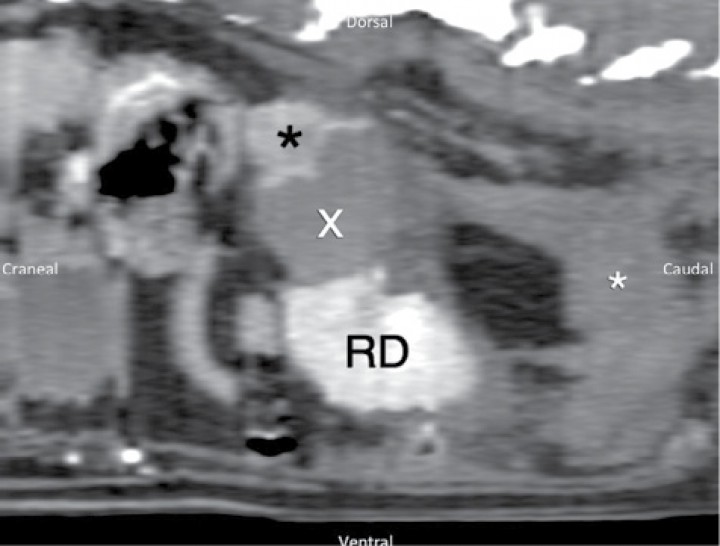

En las imágenes obtenidas por TC (Figs. 3 y 4) se observa una masa sólida en la glándula adrenal derecha con captación heterogénea de contraste (fase venosa), mostrando un valor medio de 24,4 UH (Unidades Hounsfield) antes del contraste y de 123,4 UH tras la administración de este (Iohexol, Omnipaque 350 mgI/ml, a dosis de 2,2 ml/kg, administrado manualmente). Dicha masa muestra continuidad y mantiene contacto con una masa ligeramente hiperatenuante (35 UH), la cual no muestra realce tras la administración de contraste y se extiende a través del retroperitoneo hasta la altura de L6. A su vez se visualiza una cantidad moderada de líquido libre retroperitoneal. La vena cava caudal se visualiza comprimida, parcialmente englobada y desplazada ventro-medialmente por la masa adrenal sin presentar defectos de llenado que sugieran la existencia de trombosis o invasión de su luz. El riñón derecho se observa desplazado ventro-caudalmente. Se observa una cantidad leve de líquido libre peritoneal.

<p>Imágenes de TC post-contraste en plano transversal de la región abdominal obtenidas 20 segundos después de la administración de contraste y ventana de tejido blando (WW400, WL60), ordenadas de craneal a caudal. (A) Se observa masa adrenal de aproximadamente 3,9 cm (DV) x 3,4 cm (LL) x 3,6 cm (Cr-Cd) con captación heterogénea de contraste (asterisco negro), que mantiene contacto con vena cava caudal sin mostrar invasión intraluminal, desplazándola ventro-medialmente (flecha blanca). Hematoma adyacente (x) que desplaza riñón derecho (RD) caudoventralmente. (B) Se observa la presencia de acúmulo de líquido en zona retroperitoneal (asterisco negro) y, en menor cantidad, en zona peritoneal (asterisco blanco), así como el efecto masa de la zona retroperitoneal (flechas blancas).</p>

Imágenes de TC post-contraste en plano transversal de la región abdominal obtenidas 20 segundos después de la administración de contraste y ventana de tejido blando (WW400, WL60), ordenadas de craneal a caudal. (A) Se observa masa adrenal de aproximadamente 3,9 cm (DV) x 3,4 cm (LL) x 3,6 cm (Cr-Cd) con captación heterogénea de contraste (asterisco negro), que mantiene contacto con vena cava caudal sin mostrar invasión intraluminal, desplazándola ventro-medialmente (flecha blanca). Hematoma adyacente (x) que desplaza riñón derecho (RD) caudoventralmente. (B) Se observa la presencia de acúmulo de líquido en zona retroperitoneal (asterisco negro) y, en menor cantidad, en zona peritoneal (asterisco blanco), así como el efecto masa de la zona retroperitoneal (flechas blancas).